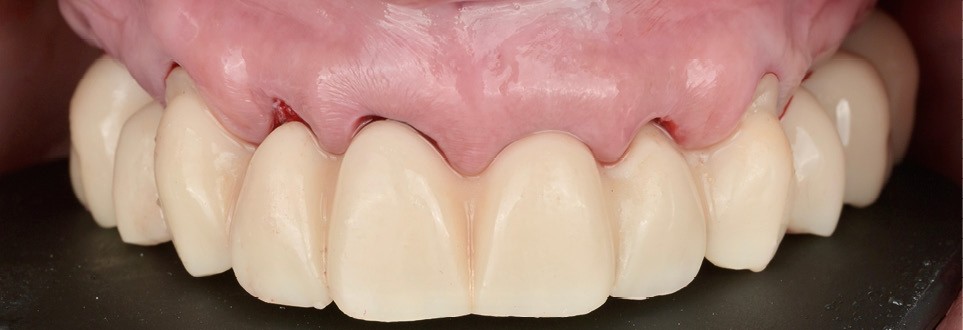

Phase prothétique et modelage tissulaire

Une empreinte numérique du positionnement des implants a été réalisée pour la conception d’une seconde prothèse transitoire guidant la cicatrisation. Cette restauration a permis de sculpter progressivement les tissus mous pour obtenir une émergence harmonieuse (fig. 7). Ces ajustements successifs ont favorisé la stabilité des papilles et la continuité du contour gingival (fig. 8) [3].